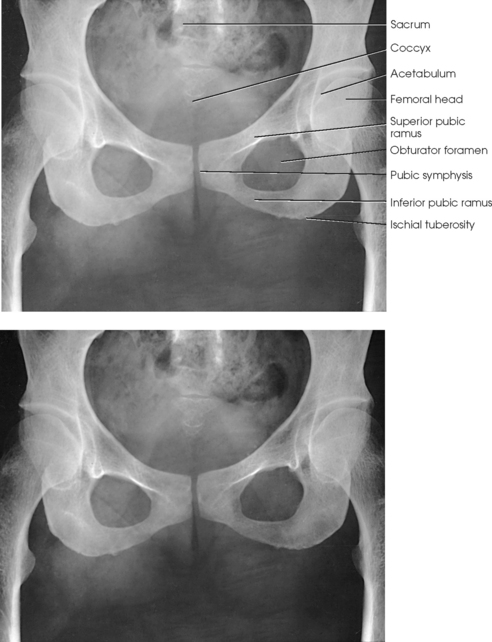

The pelvis serves as a base for the trunk and a girdle for the attachment of the lower limbs. The pelvis consists of four bones: two hip bones, the sacrum, and the coccyx. The pelvic girdle is composed of only the two hip bones.

The hip bone consists of the ilium, pubis, and ischium (Figs. 7-1 and 7-2). These three bones join together to form the acetabulum, the cup-shaped socket that receives the head of the femur. The ilium, pubis, and ischium are separated by cartilage in children but become fused into one bone in adults.

The pubis consists of a body, the superior ramus, and the inferior ramus. The body of the pubis forms approximately one fifth of the acetabulum anteriorly (see Fig. 7-2). The superior ramus projects inferiorly and medially from the acetabulum to the midline of the body. There the bone curves inferiorly and then posteriorly and laterally to join the ischium. The lower prong is termed the inferior ramus.

The ischium consists of a body and the ischial ramus. The body of the ischium forms approximately two fifths of the acetabulum posteriorly (see Figs. 7-2 and 7-3). It projects posteriorly and inferiorly from the acetabulum to form an expanded portion called the ischial tuberosity. When the body is in a seated-upright position, its weight rests on the two ischial tuberosities. The ischial ramus projects anteriorly and medially from the tuberosity to its junction with the inferior ramus of the pubis. By this posterior union the rami of the pubis and ischium enclose the obturator foramen. At the superoposterior border of the body is a prominent projection called the ischial spine. An indentation, the lesser sciatic notch, is just below the ischial spine.

The pubes of the hip bones articulate with each other at the anterior midline of the body, forming a joint called the pubic symphysis. The pubic symphysis is a cartilaginous symphysis joint.

Structures shown: The image shows an AP projection of the pelvis and of the head, neck, trochanters, and proximal one third or one fourth of the shaft of the femora (Fig. 7-18).